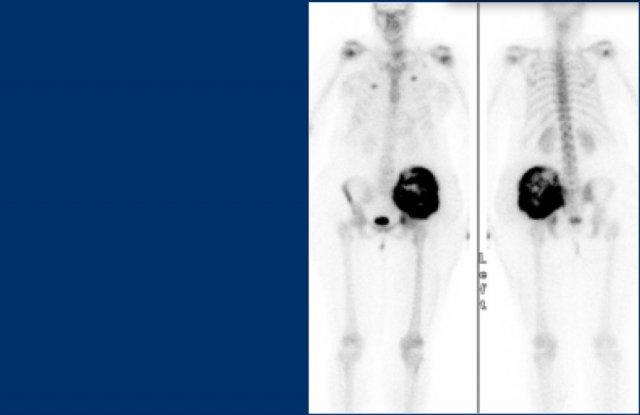

Here a chondrosarcoma of the left iliac bone.

Do kích thước lớn với sự lan rộng vào mô mềm trên phim X-quang thường và hình ảnh MRI chuỗi xung T2 trục, u sụn ác tính độ cao đã được nghi ngờ.

Biopsy showed grade 2 chondroarcoma.

Continue with the bone scan.

Hấp thu mạnh trên xạ hình xương như chúng ta có thể thấy trong u sụn ác tính độ cao.